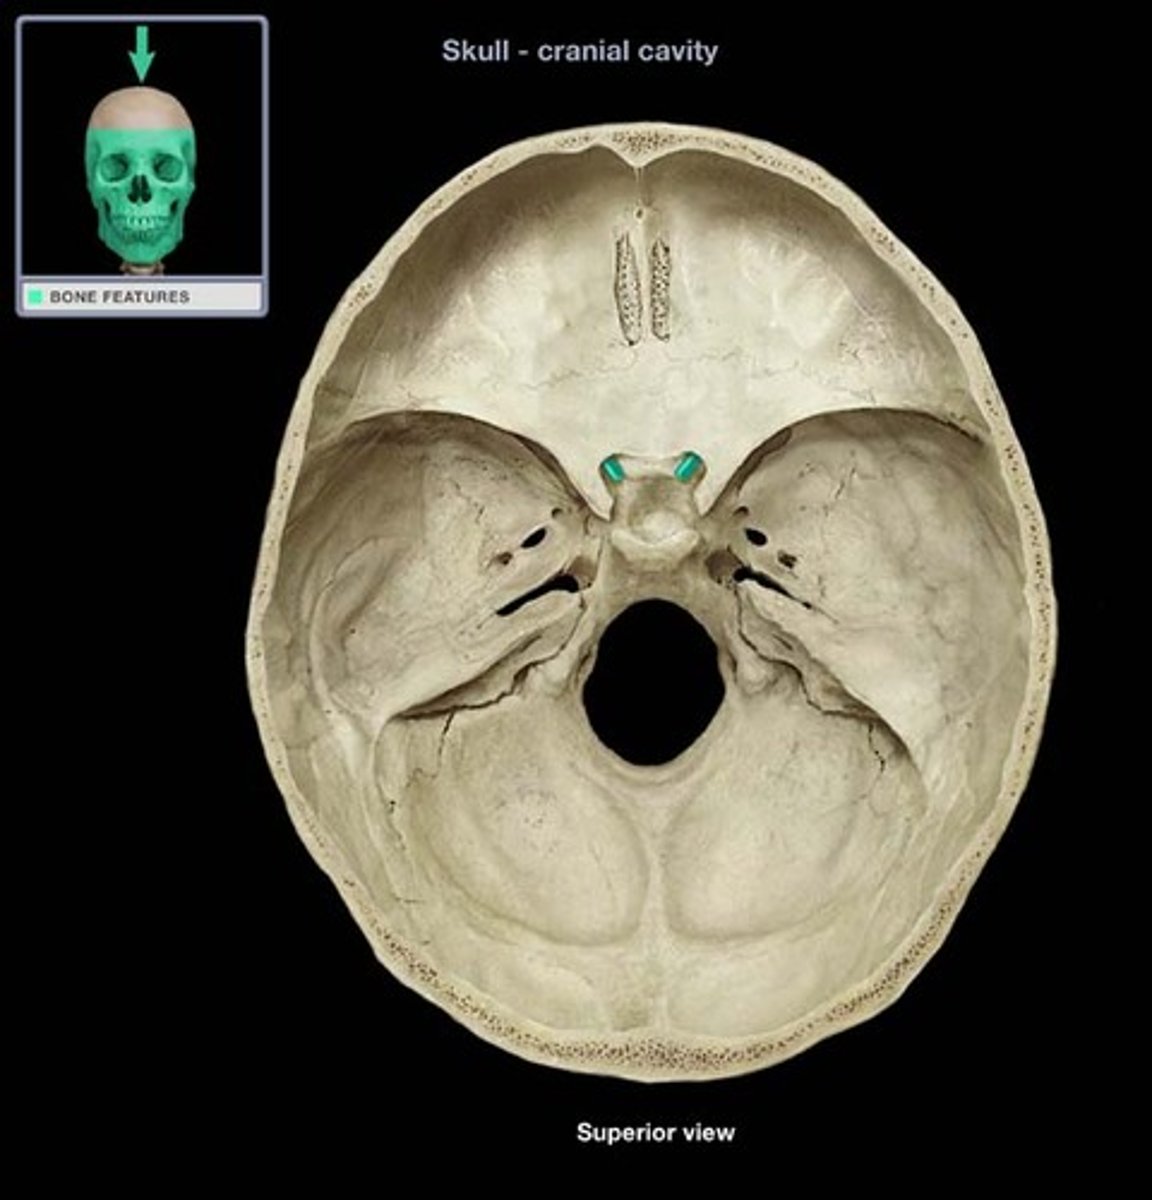

anterior cranial fossa

middle cranial fossa

posterior cranial fossa

cribriform plate

crista galli

sella turcica

tuberculum sellae

dorsum sellae

posterior clinoid processes

optic foramen